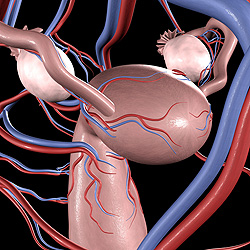

Рождение ребенка – это всегда чудо. А когда ребенок появляется у женщины, лишенной в силу генетического дефекта яичников, такое событие является чудом вдвойне. Символично, что девочка, которую назвали Виктория, родилась в пригороде Парижа в Международный женский день, 8 марта. Ее мать, Карин Тирио, страдала синдромом Тернера, из-за которого у женщины отсутствовали яичники. Более 15 лет Карин пыталась забеременеть с помощью процедуры экстракорпорального оплодотворения, однако все ее попытки заканчивались неудачей. В августе 2009 года 39-летней женщине были пересажены яичники ее сестры (также с синдромом Тернера), после чего она смогла не только забеременеть, но и родить здорового ребенка.– Впервые в мире подобную пересадку сделали близнецам, страдающим синдромом Тернера, – говорит гинеколог Жак Донне (Jacques Donnez), который провел операцию. Об уникальном случае сообщает сайт . |